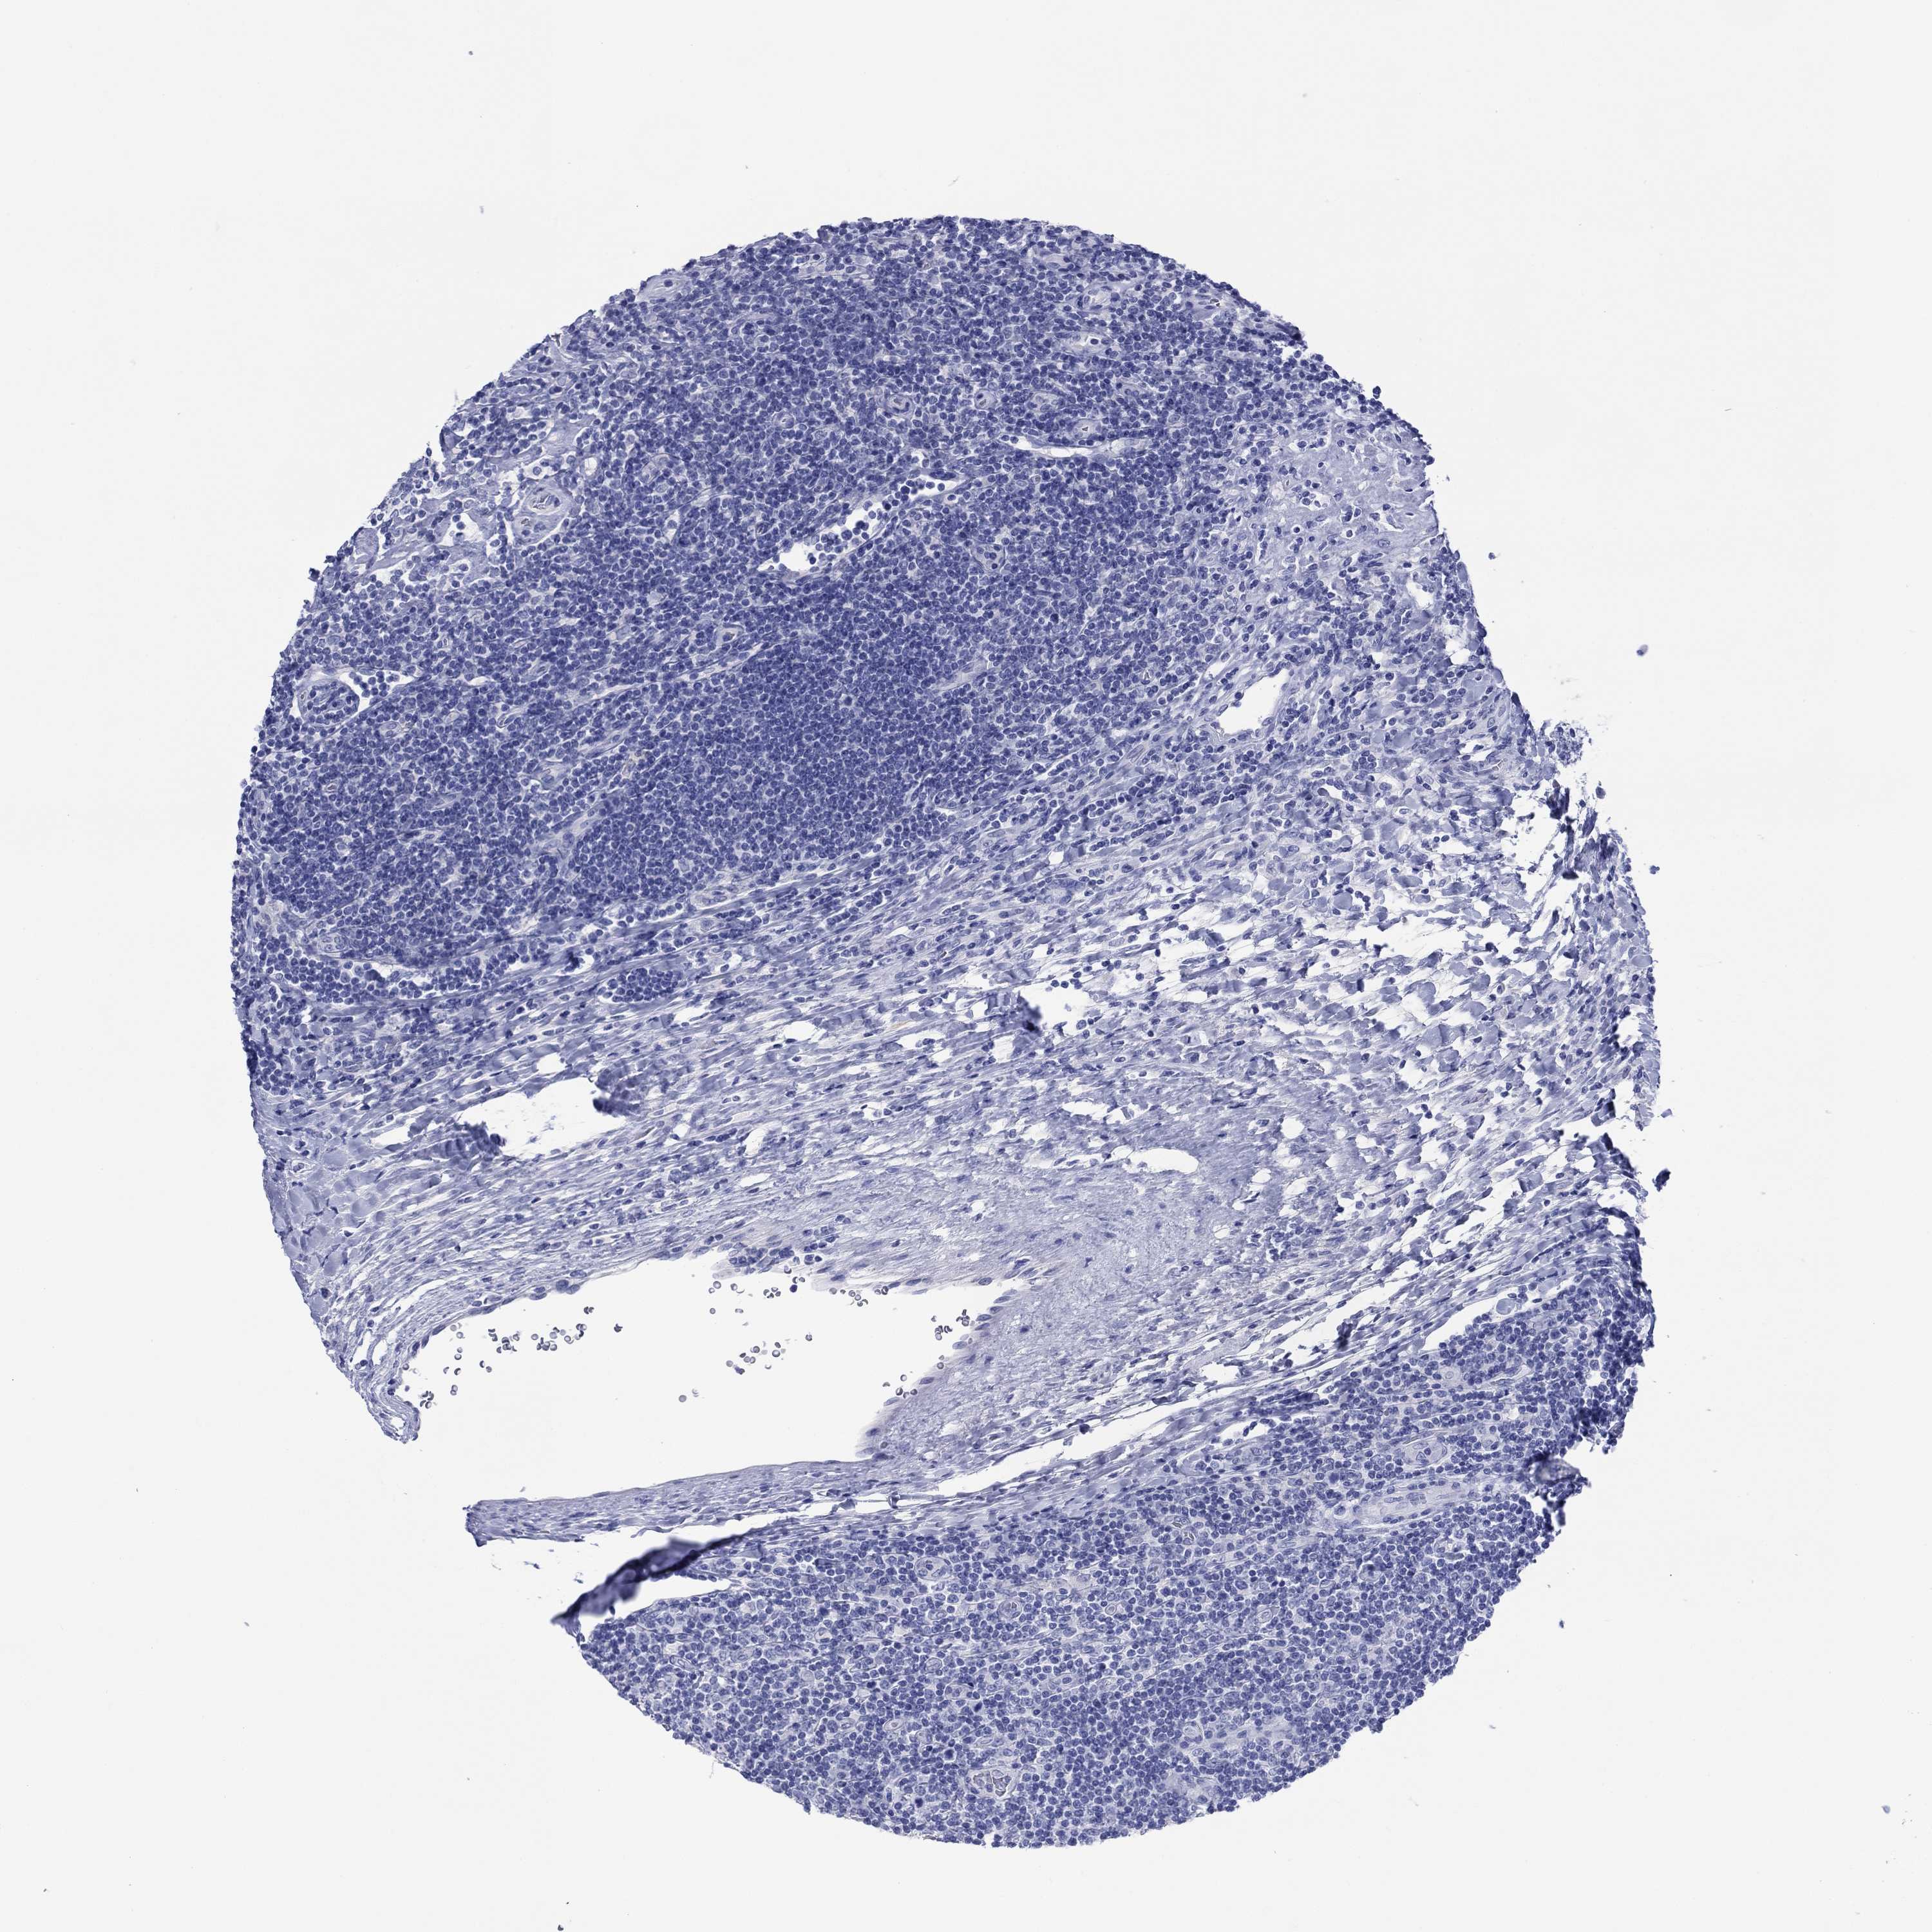

LYMPHOMA - Protein expressioni

A mouse-over function shows sample information and annotation data. Click on an image to view it in a full screen mode. Samples can be filtered based on level of antibody staining by selecting one or several of the following categories: high, medium, low and not detected. The assay and annotation is described here.

Antibody stainingi

Antibody staining in the annotated cell types in the current human tissue is reported as not detected, low, medium, or high, based on conventional immunohistochemistry profiling in selected tissues. This score is based on the combination of the staining intensity and fraction of stained cells.

Each image is clickable and will lead to virtual microscopy that enables deeper exploration of all samples and also displays staining intensity scores, fraction scores and subcellular localization as well as patient and tissue information for each sample.

Antibody HPA012911

Staining

Low

Intensity

Weak

Quantity

<25%

Location

Cytoplasmic/membranous

Hodgkin's disease, NOS